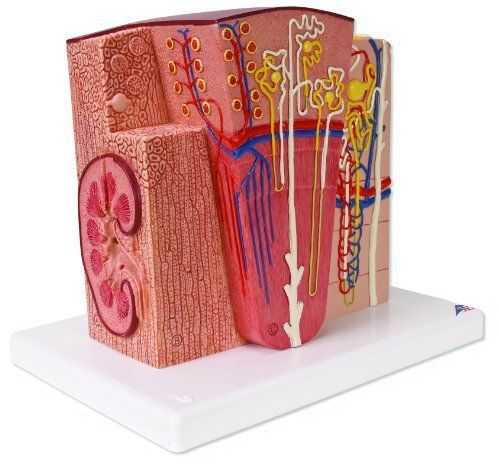

3B Scientific K13 Microanatomy Kidney Model 7.5" Length x 9.3" Width x 10" Heig